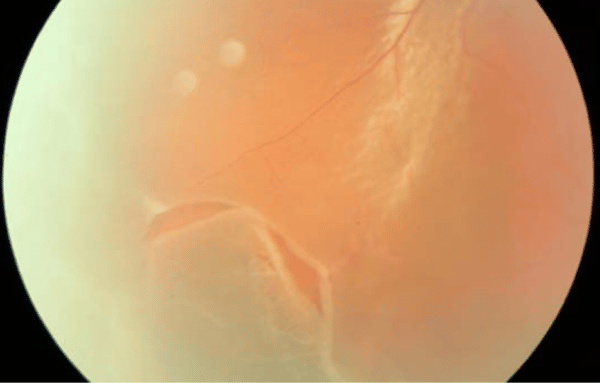

Décollement postérieur du vitré et déchirures de la rétine

Le décollement postérieur du vitré favorise la survenue de tractions vitréorétiniennes, responsables de déchirures de la rétine. La majorité de ces ruptures découlent d’une traction, qu’elle soit spontanée ou liée à un traumatisme. On estime que 8 à 15 % des cas de DVP s’accompagnent de déchirures, mais ce chiffre grimpe à 50–70 % si une hémorragie vitrée est associée.

Chez près de 15 % des patients présentant un décollement vitré symptomatique, une rupture rétinienne est constatée. Cette complication expose à un risque élevé de décollement de la rétine. En prévention, la photocoagulation au laser à l’argon est utilisée pour traiter ces ruptures. Si le traitement fait défaut, la progression vers un décollement de la rétine nécessite alors une intervention chirurgicale rapide. À noter : la moitié des patients atteints de DVP avec hémorragie vitrée présentent une rupture rétinienne, contre 8 à 15 % chez ceux sans saignement.

Chez la moitié des patients, le décollement du vitré n’est pas total : des fragments de cortex vitréen restent attachés à la rétine. La majorité des ruptures sont déjà présentes lors du premier examen, mais des déchirures tardives peuvent apparaître dans 3 à 27 % des cas.

4. Perte de vision liée à une hémorragie vitrée

Un saignement du vitré, conséquence d’une rupture ou d’une avulsion d’un vaisseau rétinien, peut entraîner une perte visuelle brutale. Ce signe doit alerter, car 50 à 70 % des DVP avec hémorragie vitrée s’accompagnent d’une déchirure de la rétine.

Face à l’un de ces signes, il est impératif de consulter rapidement. L’ophtalmologiste procède à un examen complet du fond d’œil, et renouvelle ce contrôle trois à quatre semaines plus tard pour dépister d’éventuelles nouvelles déchirures. Les ruptures détectées sont traitées au laser à l’argon, tandis qu’un décollement de la rétine nécessite en général une intervention chirurgicale.